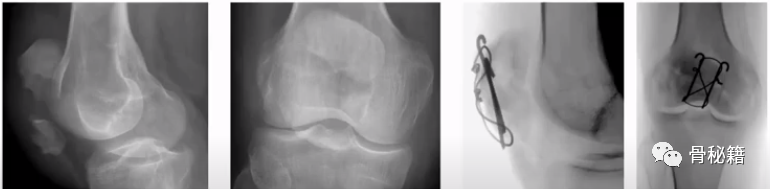

髌骨、鹰嘴,是张力带最最最常用的部位

1、髌骨骨折的初级

髌骨骨折的中级

髌骨骨折的高级